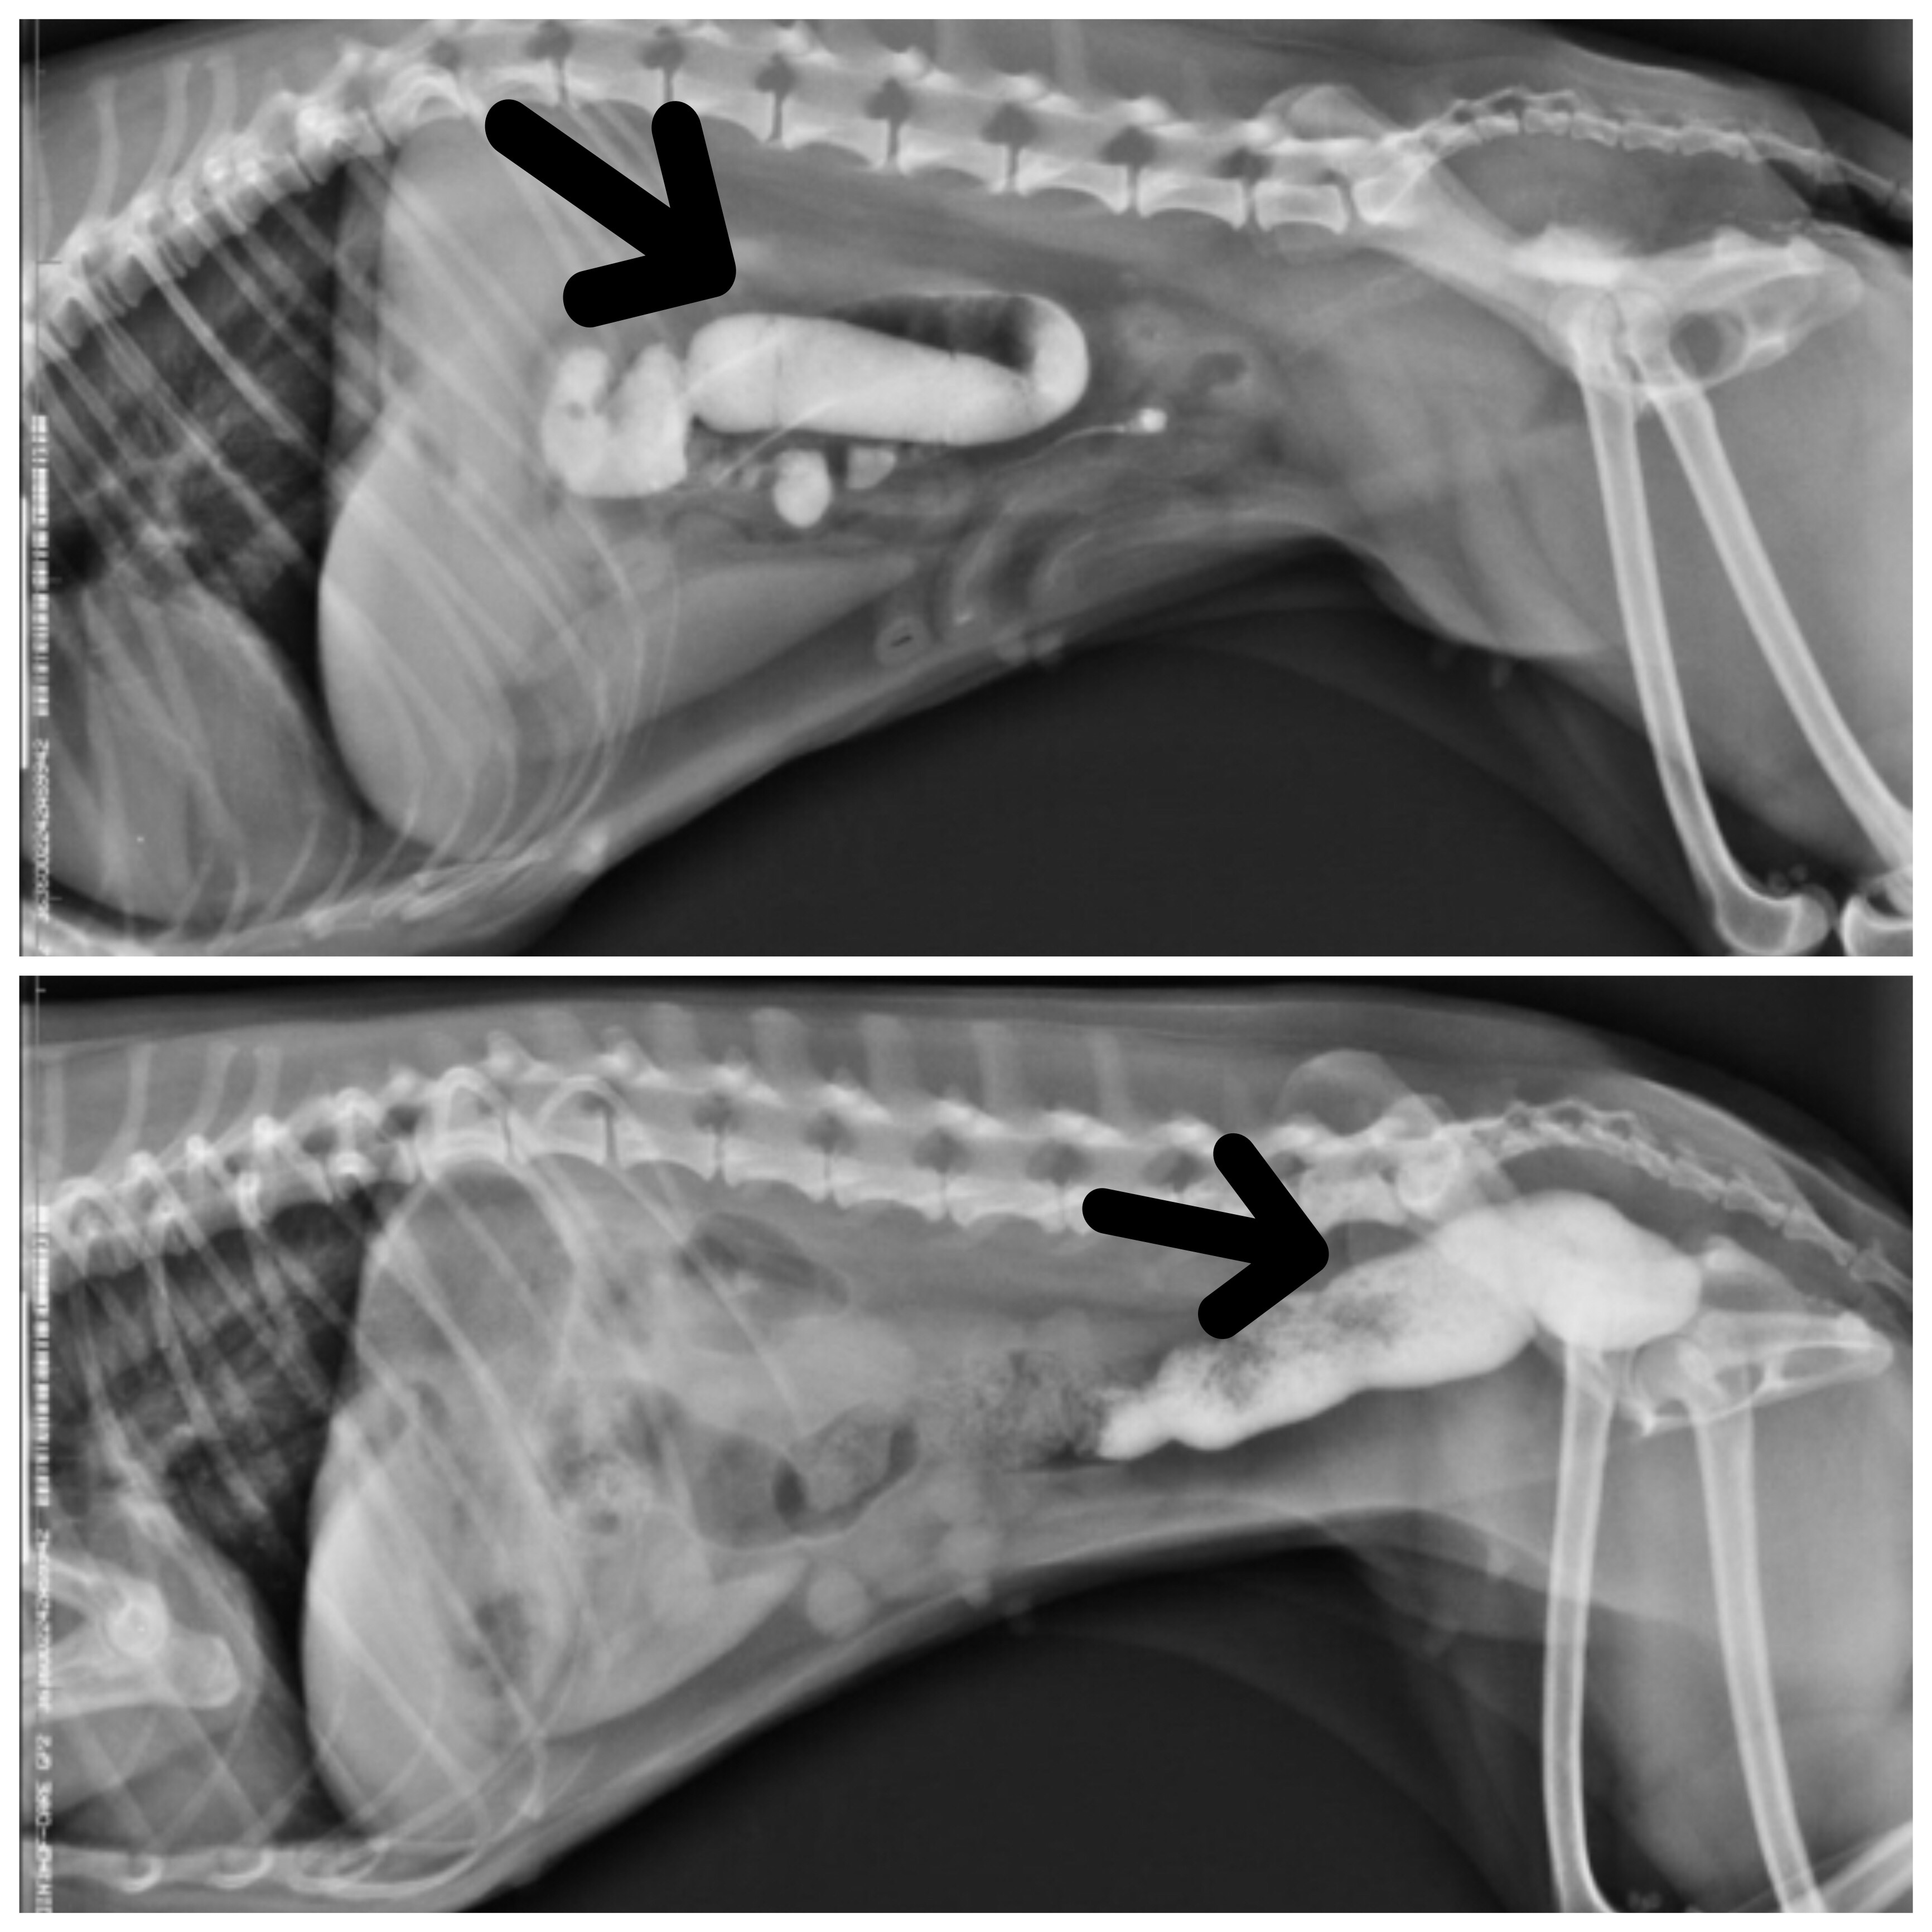

Queste sono le radiografie di una barboncina venuta in visita per vomito e costipazione. Le radiografie mostrano una zona radiopaca che indica l’enorme ingestione di sabbia che a distanza di due giorni ha raggiunto il retto. I corpi estranei possono avere forma e consistenza oppure essere microscopici, ma se ingeriti in grandi quantità, possono causare patologie subostruttive o ostruttive…quindi ATTENZIONE!!